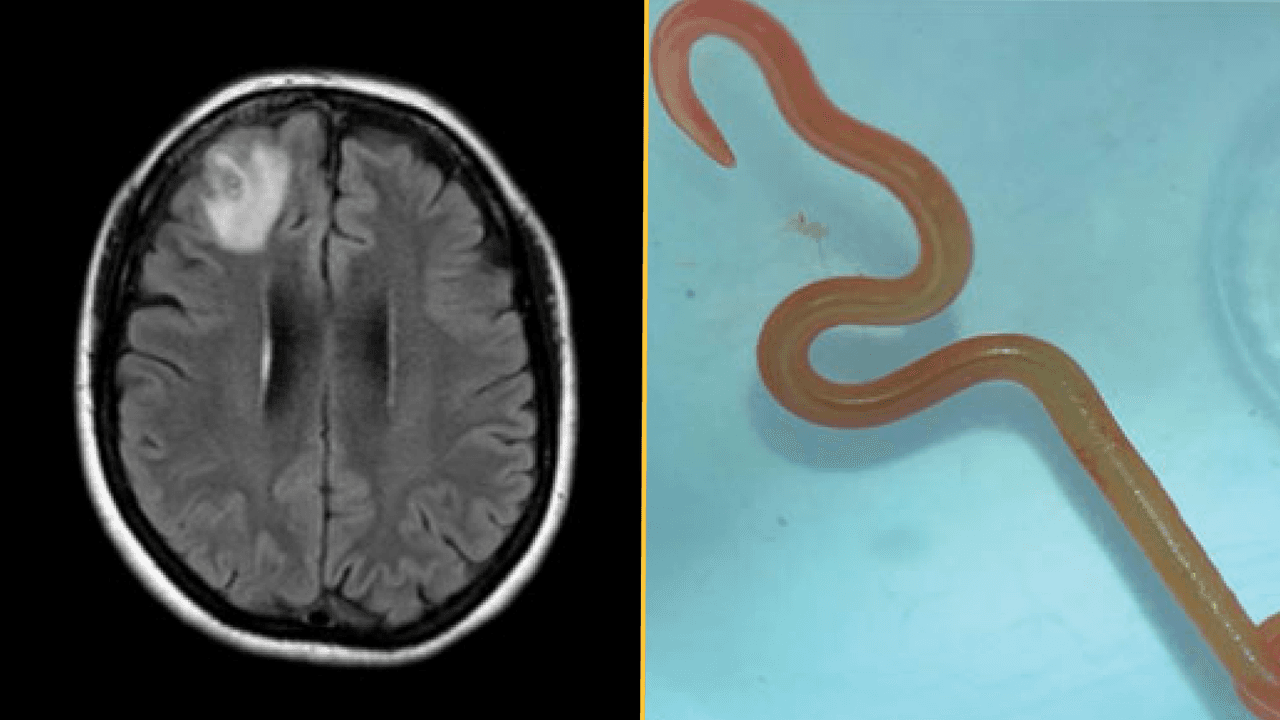

A woman developed a persistent infection, and doctors couldn't pinpoint the cause for many months.